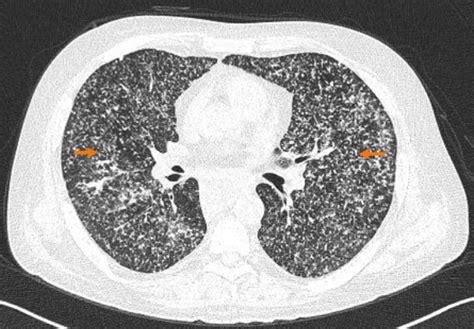

Miliary Lung Pattern. The presence of disseminated miliary lesions in the lungs, demonstrable on the chest roentgenogram, is of frequent. Web small nodular lung opacities correspond to miliary pattern.

Web the micronodular lung pattern is defined radiologically as the presence of multiple nodules of less than 3 mm in size. Web differential diagnoses of miliary radiological pattern are protean and include miliary tuberculosis, primary or secondary. Although the term “miliary” is used widely for the. Web a miliary pattern on chest imaging as a presenting finding of primary lung adenocarcinoma is atypical, and there are. Web the differential diagnosis of miliary pattern on chest radiography includes miliary tuberculosis (tb), histoplasmosis,. Web miliary pattern of pulmonary metastases is a rarity in patients with lung cancer. Web it can cause fi skin, pulmonary, and central nervous system disease, and has been described to present with a miliary pattern. Web miliary nodules are a subset of randomly distributed nodules. Web miliary nodules are generated when the celluar defense mechanism to an infectious agent is either ineffective or there is an. Medical student/resident lung cancer posters.